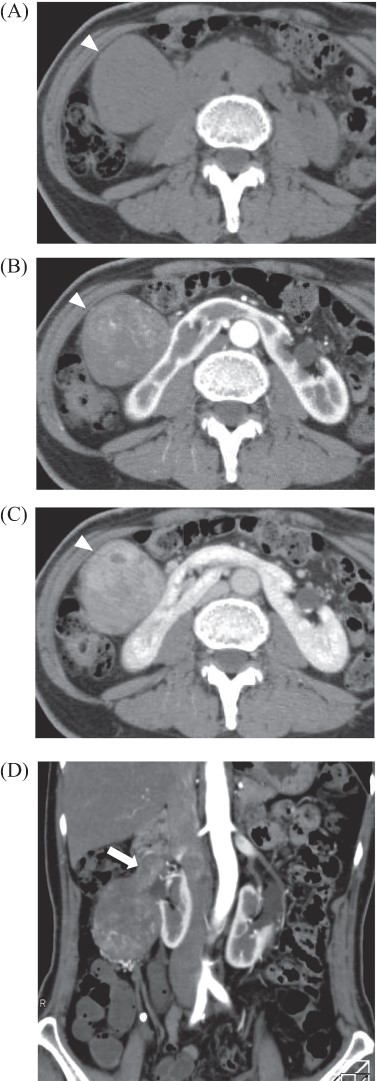

A 69-year-old woman presented to our institution with right abdominal pain. There was nothing special to mention in her family history. Her past medical history included horseshoe kidney, gastric ulcer, and asthma. Physical examination revealed a slight tenderness of the right quadrant abdomen. All laboratory parameters including the tumor markers carcinoembryonic antigen and carbohydrate antigen 19-9 were within normal limits. Abdominal ultrasonography showed a regularly shaped uniform tumor of about 50 mm in diameter that was located in the right retroperitoneum ventral to the right part of the horseshoe kidney. The tumor was hypervascularized (Fig. 1). Computed tomography (CT) showed a tumor of 80 mm in diameter ventral to the right part of the horseshoe kidney and the dorsal side of the descending part of the duodenum. On contrast-enhanced CT, the tumor showed late-phase enhancement. There were no findings of invasion into any organs and right ovarian vein ran through the tumor (Fig. 2). No metastases to organs or swollen lymph nodes were found. Magnetic resonance imaging (MRI) showed a tumor that was isointense with respect to muscle on T1-weighted images and of high-signal intensity on T2-weighted images (Fig. 3). No fatty components were detected in the tumor. Endoscopic ultrasonography showed a regularly shaped and hypoechoic tumor with no connection to the right part of the horseshoe kidney or duodenum (Fig. 4). Our working diagnosis was a retroperitoneal tumor that could be either a malignant lymphoma, leiomyoma or gastrointestinal stromal tumor.

Abdominal MRI: tumor revealed iso intensity with muscle in T1 weighted image (A), slightly high intensity in T2 weighted image (B) and abnormal signal in diffuse weighted image (C).